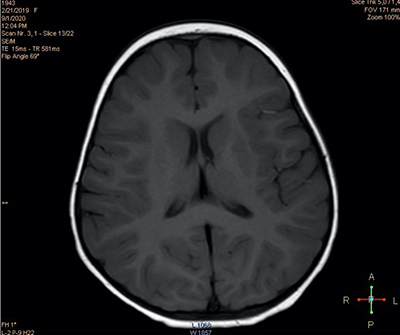

При проведении нейровизуализационного исследования (МРТ 2 Тл) выявлены признаки некоторого усиления МР-сигнала в парагиппокампальной области (см. рис. 2а) и незначительного расширения переднего субарахноидального пространства (см. рис. 2б), что может свидетельствовать в пользу перенесенной гипоксически-ишемической перинатальной энцефалопат На третьи сутки количество эпизодов отведения глаз сократилось до 6, при этом их продолжительность не превышала нескольких секунд.